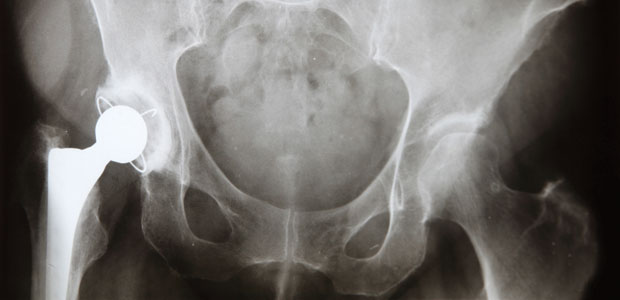

Osteoporosis